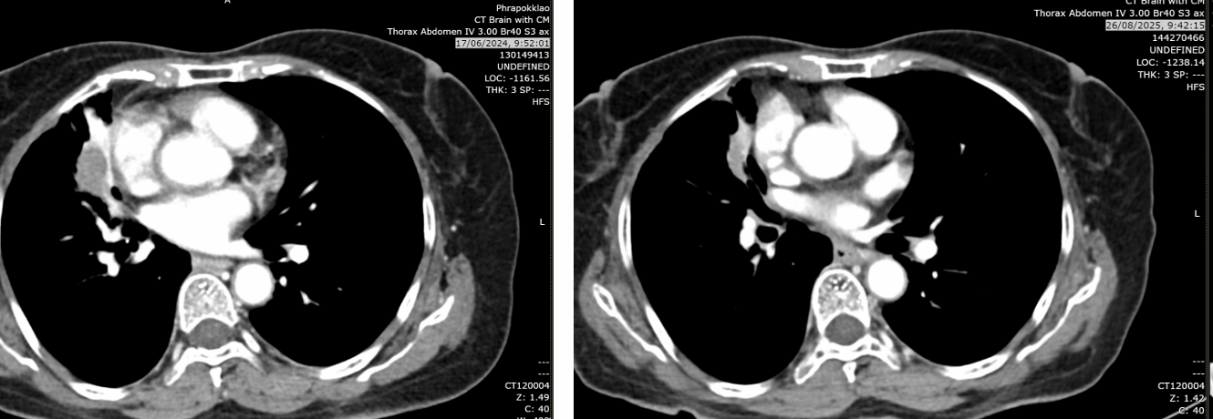

2024年6月17日:肿块略增至2.9cm,亚厘米级淋巴结。

2025年8月26日:肿块2.2cm,右肺上叶、中叶结节0.3-0.4cm稳定,中叶新增磨玻璃影(考虑感染或炎症),无新增转移灶。